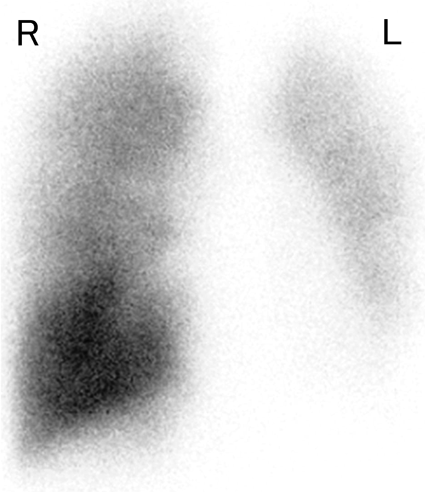

先天性片側肺静脈狭窄に対側のAnomalous Unilateral Single Pulmonary Veinを合併した1例A Case of Congenital Unilateral Pulmonary Vein Stenosis with Contralateral Anomalous Unilateral Single Pulmonary Vein